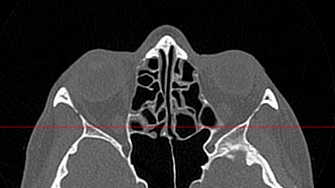

Воспалительные заболевания, такие как гайморит или синусит верхнечелюстных пазух, этмоидит, сфеноидит и фронтит достоверно визуализируются при помощи компьютерной томографии. Полученные данные помогают врачу специалисту в верификации диагноза и утверждении эффективного плана лечения. На фоне воспалительных изменений нередко встречаются полипозные образования, а при запущенных случаях синуситов очень важно подтвердить или исключить наличие участков деструкции костных перегородок.

Что показывает КТ носа

- полипы;

- опухоль (злокачественная и доброкачественная);

- инородные тела в указанной области;

- воспалительный процесс (утолщение слизистой оболочки, жидкость, признаки гноя);

- повреждение костей.